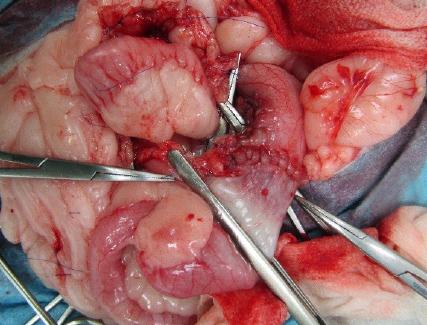

| 症状 | 3日前より食欲不振と嘔吐、下痢を主訴に来院されました。腹部触診にてお腹のなかにしこりが触知されました。エコー検査を行ったところ、左上腹部に腎臓腫瘍が認められました(図1)。オーナー様とご相談の上、摘出することにしました。 |

| 手術方法 | 全身麻酔下で開腹を行い、腎臓腫瘍の摘出を行いました(図2~3)。また、同時に膀胱内結石の摘出も行いました(図4)。 |